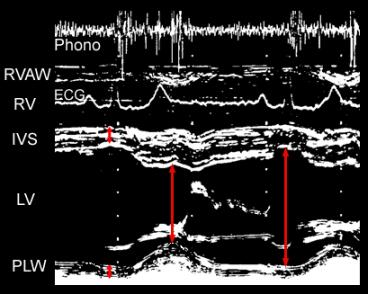

M-Mode examination of the left ventricle using short axis diameters

Measurement of LV diameters (cm):

End-diastolic at Q wave of ECG

End-systolic at either:

a) end-systolic notching of IVS

b) first wide component of II heart sound (phonocardiogram)

c) maximum anterior position of posterolateral wall

Fractional shortening of LV diameters

[(end-diastolic - end-systolic) / end-diastolic] x 100

IVS: interventricular septum  室间隔

LV: left ventricular cavity  左室容积

Phono: phonocardiographic tracing  心音淼记

PLW: postero-lateral wall  心室后侧壁

RV: right ventricular cavity  右心室容积

RVAW: RV anterior wall  右室前壁